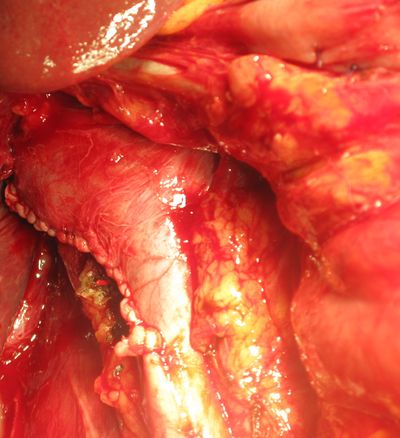

Ушитая нижняя полая вена после удаления тромба